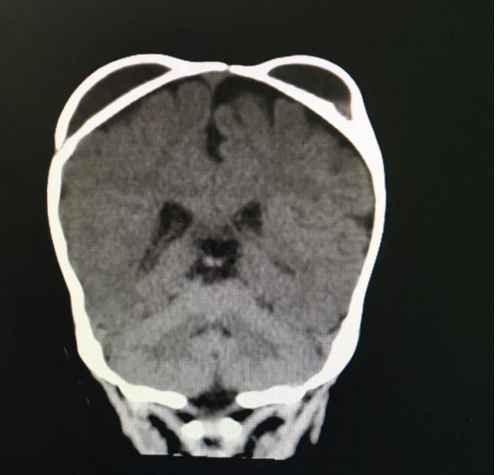

我院神经外科近期收治了多例头上长“犄角”的宝宝,CT成像宛如一个大熊猫,肿包摸起来感觉越来越紧实,边缘清楚,这是血肿机化后变硬所致